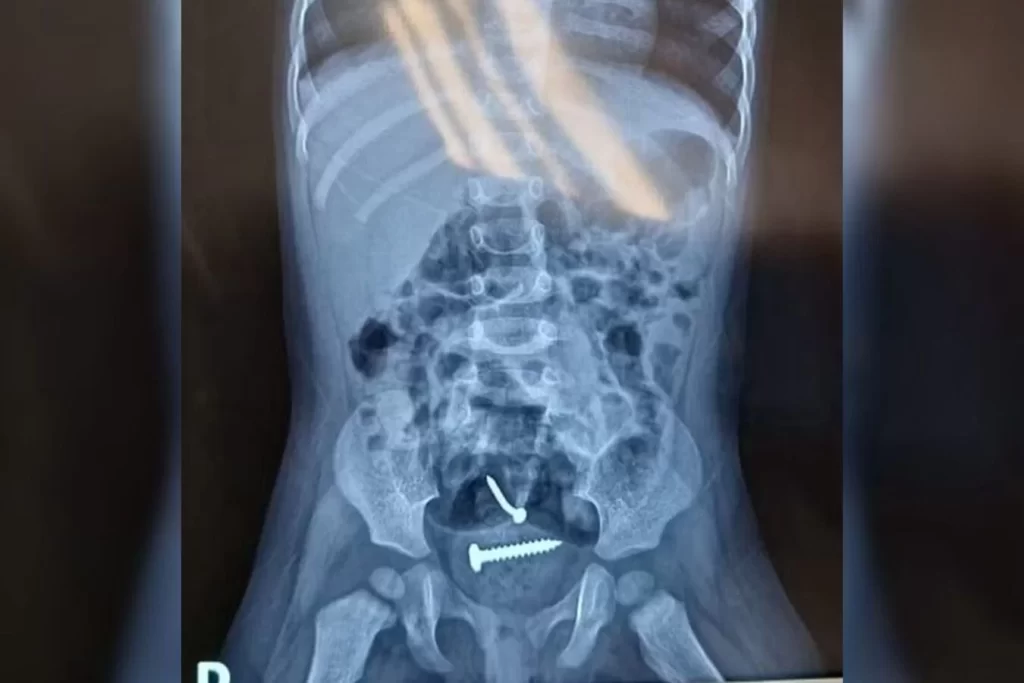

Elas foram encaminhadas para o hospital e, após a realização dos exames, um raio-X apontou a presença de objetos estranhos dentro do corpo da menina. Ela também tinha lesões nas partes íntimas.